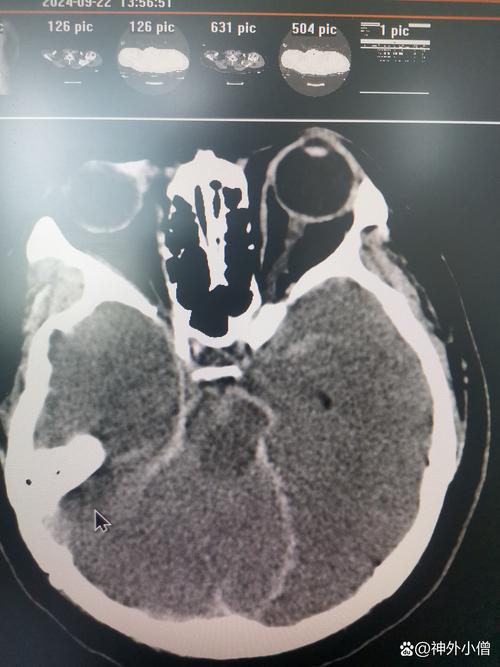

周边水肿效应

- 出血灶周围通常会有一圈低密度(黑色)的水肿带,这是血液成分刺激脑组织引起的炎性反应和细胞毒性水肿,水肿范围越大,占位效应越明显。

占位效应与中线移位

- 这是评估出血严重程度的关键指标。

- 占位效应: 血肿和周围水肿会挤压、推移正常脑组织。

- 中线移位: 如果出血发生在大脑一侧,会推挤大脑镰(大脑中间的硬脑膜),在CT上可以看到中线结构(如脑室、脑沟)向对侧偏移,中线移位超过5mm通常被认为是比较严重的情况,需要紧急处理。

破入脑室系统

- 如果出血量大或靠近脑室,血液可能破入脑室,导致脑室内出现高密度影,这会堵塞脑脊液循环通路,引起急性脑积水,使病情急剧恶化。